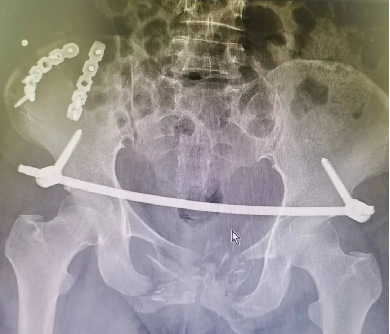

案例三

創傷性骨盆骨折致尿道斷裂患者,膀胱(guāng)造瘺術後,需穩定骨折端(duān)避免二次傷害。

骨盆前環微創經皮內固定技術(INFIX技術)固(gù)定結合了內固定和外固定的優點,揚長(zhǎng)避短,針對此類(lèi)患(huàn)者,有效避免了術後深部感染,又避(bì)免(miǎn)了使(shǐ)用外固(gù)定的手術並發症,讓患者在最佳(jiā)治療時機獲得了骨盆環的穩定,並能早期開始功能鍛煉,最大程度上降低了因傷致殘的機(jī)率。